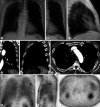

The lead author with clinical stage I malignant pleural mesothelioma, epithelioid type, highly programmed cell death ligand 1 (PD-L1) positive, and BAP1 negative, experienced a prompt and exceptionally favorable response to pembrolizumab monotherapy. After cessation of treatment due to immune-related endocrinopathies, complete metabolic response on interim PET/CT scan was achieved. Two years after initial diagnosis, unifocal tumor reactivation was addressed with successful pembrolizumab monotherapy rechallenge. Immunotherapy, typically not used as frontline treatment for malignant pleural mesothelioma, may provide an effective and durable response for some patients. Based on this single case study, epithelioid type tumors with strongly positive PD-L1 and BAP1-negative immunohistochemical markers may be well suited for treatment with immune checkpoint inhibitors such as pembrolizumab.